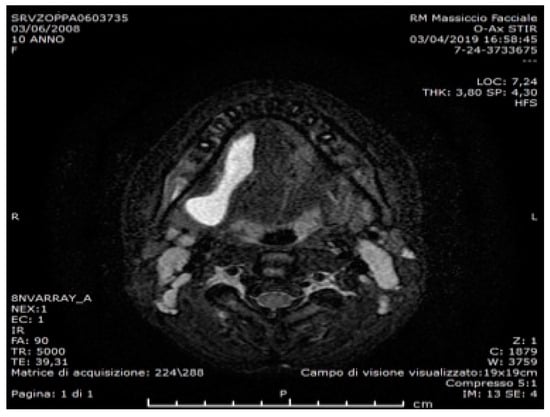

2. Case Report